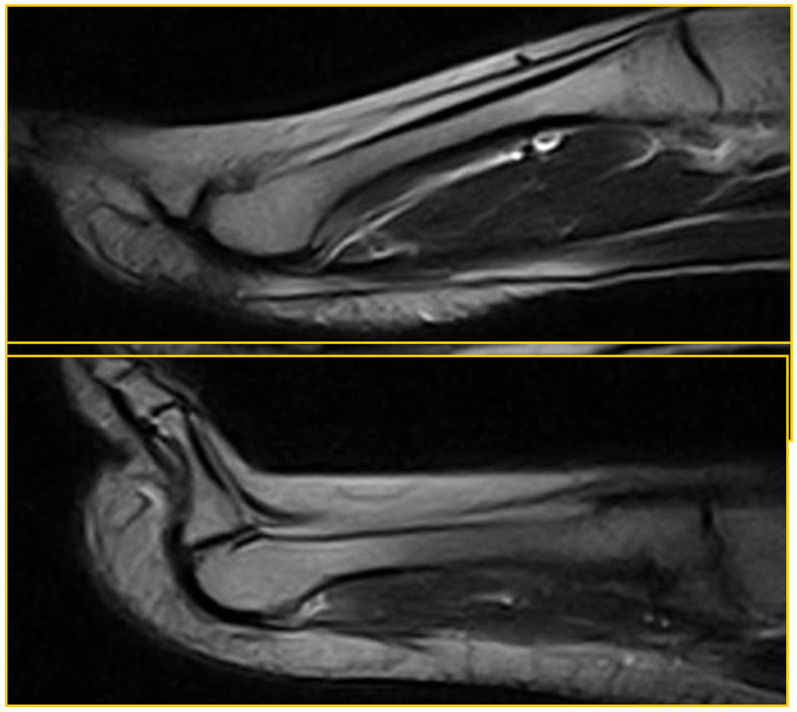

Materials and methods: All patients underwent forefoot MRI (Atroscan C, Esaote, Genoa, Italy), operating at 0.2 T. All patients first underwent a standard MRI examination (coronal T1 and T2 weighted image (WI) with fat suppression and axial and sagittal T2 WI); the examination was completed by performing a stress test (hyperextension of toes). The ST is an easy task to perform and is not time-consuming (requiring only one additional sagittal fast spin echo (FSE) T2-weighted MRI sequence; repetition time/ echo time (TR/TE): 3200/90 ms) for patients and operators. A 45°-dorsiflexion ST was performed for approximately 2.30 min, the time required to complete the sequence. No further diagnostic investigations were necessary; no patients underwent arthrography or arthro-MRI. The examinations were performed in a double-blind mode by two operators with proven experience in musculoskeletal radiology; no cases of intra-operator discordance were found.

Results: Twenty-five patients were recruited into our study over a 2-year period; 15 were positive for metatarsal pain and 10 were controls. Before treatment (surgery), all patients displaying symptoms underwent evaluation. As a result, the imaging features accurately represented the natural and actual conditions of the lesions. Among the symptomatic patients, 11 out of the 15 exhibited a PP tear or dysfunction in both the standard position and the ST. Additionally, two out of the 15 individuals displayed a tear in the ST alone, with no indication of it in the standard position. In contrast, two out of 15 patients showed no evidence of a PP tear in either the standard position or the ST. However, these two patients demonstrated dorsal subluxation during the ST, likely due to micro-instability resulting from PP failure. In the asymptomatic patients, nine out of the 10 individuals were found to be negative for PP dysfunction. Only one out of the 10 patients exhibited dorsal subluxation solely in the ST, indicative of plantar plate dysfunction, but no evidence of a tear in the PP. In the asymptomatic patients, standard MRI provided a specificity of 100% and a high negative predictive value (NPV) (90%), while the latter increased with the ST (specificity and NPV equal to 100%). In symptomatic patients, standard MRI gave a sensitivity of 75% when assessing a PP tear, which increased to 100% with the ST; the sensitivity of standard MRI the evaluation of MF subluxation was 60%, but it reached 100% with the ST.